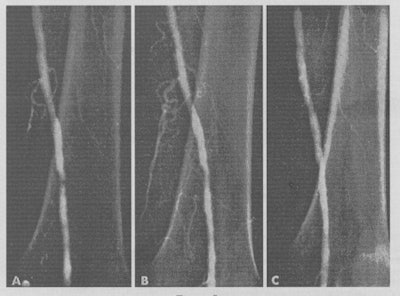

Case one from Circulation, published in November 1964. A: The control angiogram showing threadlike lumen in the region of the adductor hiatus. B: The angiogram performed immediately after dilatation with a 3.2-mm OD catheter. C: The angiogram performed at three weeks.The classic paper on Transluminal Treatment of Arterial Obstruction appeared in Circulation in November (1964, Vol. 30, pp. 654-670), and a total of 10 cases were described. Dotter and co-author Dr. Melvin Judkins wrote in the opening paragraph: "Despite the frequency and importance of arteriosclerotic obstruction, current methods of therapy leave much to be desired. Nonsurgical measures, however helpful they may be, provide the patient little more than an opportunity to live with his disease."

Ten days later, Dotter performed a percutaneous transfemoral catheter dilatation of the segmental femoral narrowing, and he recorded that it took only a matter of minutes and was performed without difficulty. When the dilating catheter was removed, good pulses were palpable for the first time in the lower leg and foot. Angiography revealed that the stenosis was no longer present. There was immediate diminution in pain, discoloration, and coldness of the foot. During the week after the procedure, there was rapid healing of the ischemic skin changes, including the ulceration of the lower leg.

A follow-up angiogram was performed on 6 February, three weeks postprocedure, and the lumen remained patent. At eight months, the patient was ambulatory, the ulceration was gone, the gangrenous toes had separated, and the sites were healed. The patients' pain disappeared, and she was able to walk until she passed away three years later.